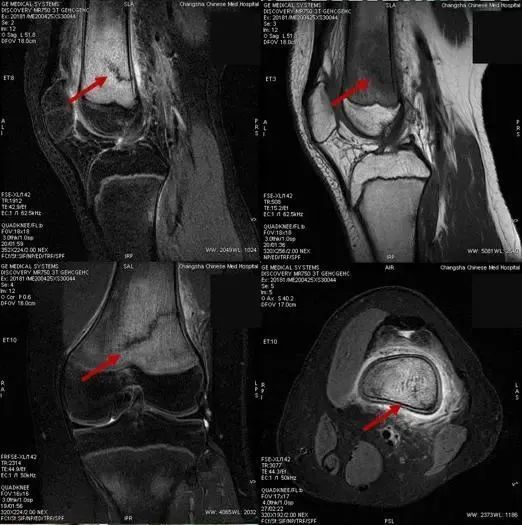

4月27日,湖南长沙市中医医院(长沙市第八医院)放射科 MR 技术组长周飘华与正在阅片的医师陈婷婷讨论。

近三天来,科室陆续诊断了7例“应力性骨折”患者,这7名患者有一个共同点:都是14~15岁的青少年

15岁的罗同学,因“右膝关节肿痛,加重1天”入院,在行膝关节磁共振成像检查时,发现“右侧股骨下段骨折并广泛骨髓水肿”

通过仔细询问病史发现,这名疫情期间新近返校的初三学生,因邻近中考需要参加体育考试,每天都进行了一定强度的体育训练,最近几天出现膝关节疼痛明显加重,于是罗同学妈妈带他到医院就诊。

无独有偶,很快,又有三名同学陆续来院就诊,他们的情况与罗同学完全一样,都是14~15岁的初中生,在学校参加跑步等体育锻炼后出现膝关节疼痛,并加重后就诊,经磁共振成像检查,被诊断为应力性骨折

应力性骨折通过普通X线片往往无法发现问题,容易发生漏诊,需要结合病史、查体,并配合磁共振检查来确诊诊断。